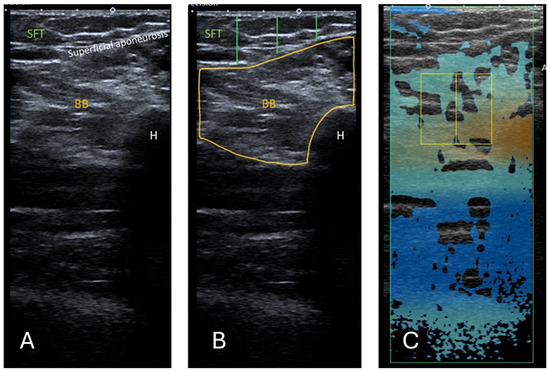

Background/Objectives: Sarcopenia, an underdiagnosed musculoskeletal disorder, is a serious cause of disability, poor quality of life, and healthcare costs in an increasingly elderly population. This study aimed to examine an ultrasound (US)-based, inexpensive, simple, and reproducible alternative to magnetic resonance imaging (MRI) for assessing muscle quality. A study compared Dixon MR fat fraction with US attenuation imaging (ATI) and echo intensity (EI) in the rectus femoris (RF) and biceps brachii (BB). Methods: The US images were acquired from 34 participants who had previously received a whole-body MRI. The ATI measurements were carried out using a linear array on a Canon Aplio i800 scanner. The measurements of EI were assessed by manually tracing the cross-sectional border of the right RF and BB muscles. Corresponding T1-weighted Dixon VIBE-based fat and water images were required for the MRI fat fraction percentage (MR %FF) measurements. Results: Using Pearsons correlation coefficient, a good correlation was found between MR %FF and EI measurements. The results between operators’ measurements showed a strong correlation and were highly repeatable. Attenuation imaging revealed no correlation with MR %FF or EI. Conclusions: Echo intensity offers a low-cost, non-invasive, and widely accessible US-based imaging modality for screening patients at risk for sarcopenia. No correlation was found between the ATI and MR %FF or between the ATI and EI. Further adapted protocols and software adjustments are needed so that ATI has the potential to prove itself as an additional US-based method for assessing fat infiltration in muscles. Full article

Show Figures

Figure 1